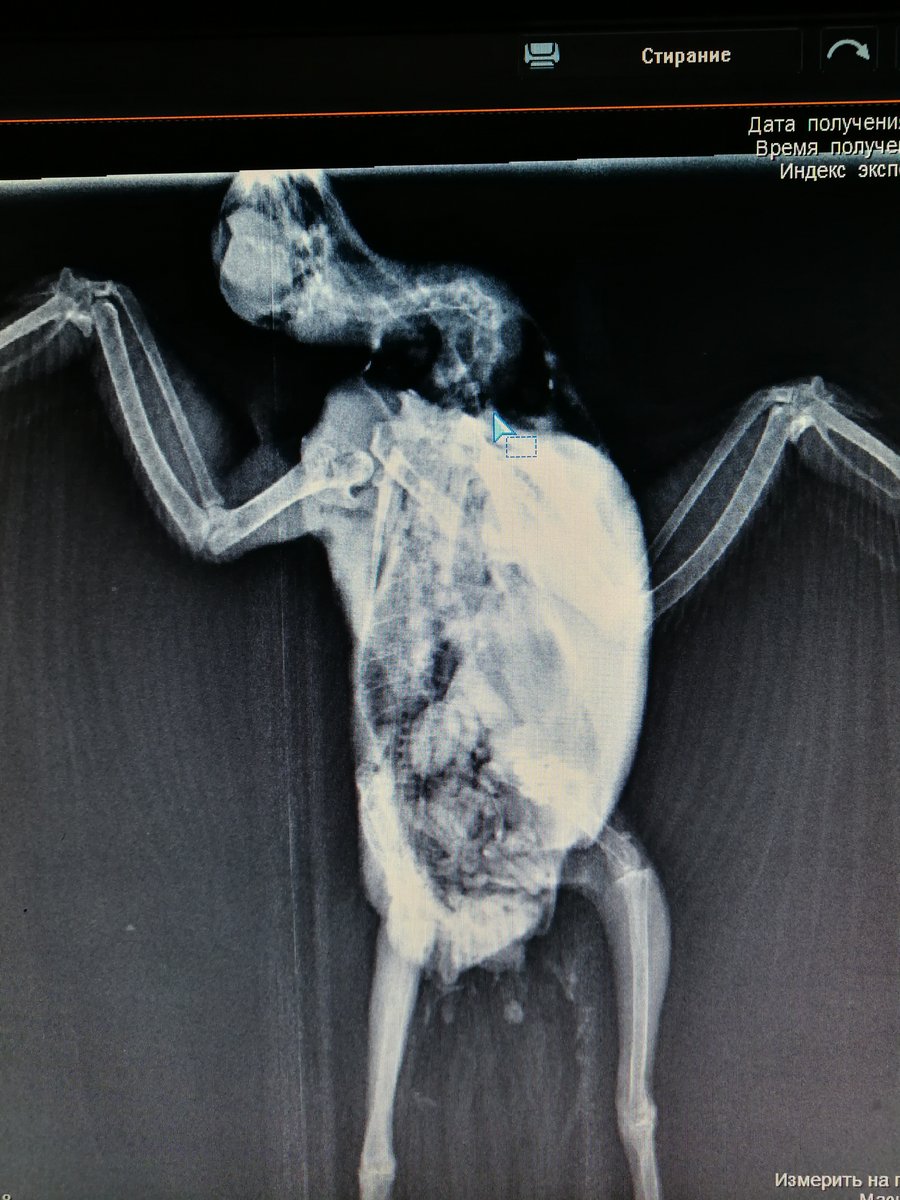

Elena1811 Опубликовано 7 марта, 2020 Автор #113 Опубликовано 7 марта, 2020 Мы старались как могли. Не получается его развернуть полностью из-за левого крыла. Не разворачивается доконца. Боялись сломать

Zosia Опубликовано 7 марта, 2020 #124 Опубликовано 7 марта, 2020 Если есть файлы на флешке- то мне на почту киньте. Т.к. в переснятом виде снимки нечитабельны. zofia68@mail.ru

Elena1811 Опубликовано 11 марта, 2020 Автор #130 Опубликовано 11 марта, 2020 Получила ответ от Зофии. Нужны разъяснения. И некоторые препараты я не могу купить Вот что пишет Зофия: Ну, отличить голубя от голубки я по фото не смогу. Хотя ИМЪО мне видится голубка. И те новообразования в брюшной полости (которые могцт передавливать нервные окончания, идущие к лапкам)- характерны именно для голубок, у меня даже фото есть гранулем, которые у них «рождаются» вместо яиц. Так что ИМХО- итраконазол в дозе 15 мг/кг каждые 12 чсов, нисиатин в дозе 75 000 ед в сутки на 100 гр веса, преднизолон из арсчета 3 мг/кг в сутки. Первый курс- 21 день. Для прикрытия преднизолона- Деринат капли назальные, принимать орально 4 капли в сутки весь курс. Обязательно гепатовте- 0,2-0,3 мл в сутки. По крылу- ваш снимок не дает возможности оценить фатальность нарушений. Но скорее всего- там уже вряд ли что можно сделать (и по-любому это вопрос-не вопрос жизни). ......... У нас беда с преобретением лекарств, рецепты только лишь на аналгин не нужны..